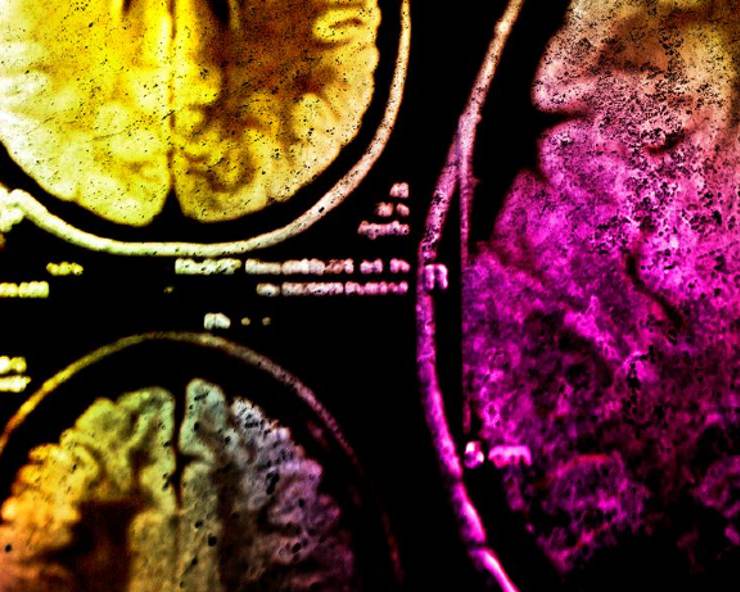

इन्वेसिव कैंसर ब्रेस्ट कैंसर (Breast cancer) का प्रकार होता है और अधिकतर महिलाओं में इन्वेसिव ब्रेस्ट कैंसर से ही पीड़ित होती हैं। इन्वेसिव कैंसर महिलाओं के ब्रेस्ट टिश्यू (breast tissue) पर आक्रमण करता है और धीरे-धीरे ये हमारे पूरे शरीर में फैल जाता है।

1. Invasive Ductal Carcinoma (IDC)- ये प्रकार सबसे सामान्य है और ये 80% ब्रेस्ट कैंसर का कारण होता है। ये कैंसर ब्रेस्ट में मिल्क डक्ट (milk duct) से शुरू होता है और वॉल्स (walls) को तोड़कर ब्रेस्ट के टिश्यू में आक्रमण करता है। ये कैंसर टूमओर के स्थान से शुरू होता है और धीरे-धीरे पूरे शरीर में फैल जाता है।

2. Invasive Lobular Carcinoma (LIC)- ये प्रकार ब्रेस्ट कैंसर का 10% कारण होता है। ये कैंसर महिलाओं के मिल्क ग्लैंड (milk gland) से शुरू होकर पूरे शरीर में फैल जाता है। इस प्रकार के इन्वेसिव कैंसर के कारण महिलाओं के ब्रैस्ट पर गांठ नहीं होती बल्कि उनके ब्रैस्ट उमड़ना शुरू हो जाते हैं।